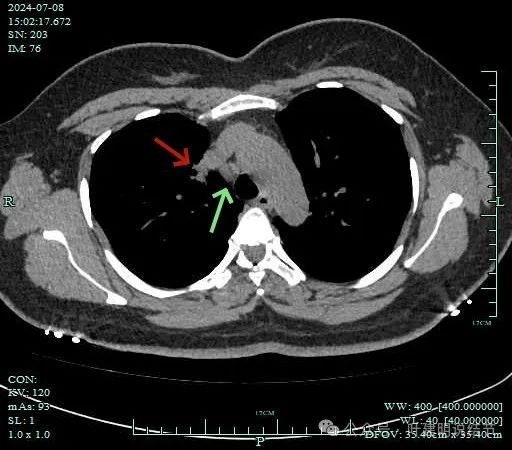

再看2024年7月份的影像:

病灶纵隔窗上是软组织影,表面不平,形态不规则。上腔静脉旁有肿大淋巴结。

灶边部分细支气管扩张,腔静脉旁淋巴结较大

病灶有血管与之相连,淋巴结更显得明显了。

隆突下明显肿大淋巴结

左侧肺门与纵隔肿大淋巴结

双侧肺门与纵隔明显肿大淋巴结。

右侧腔静脉旁肿大淋巴结。